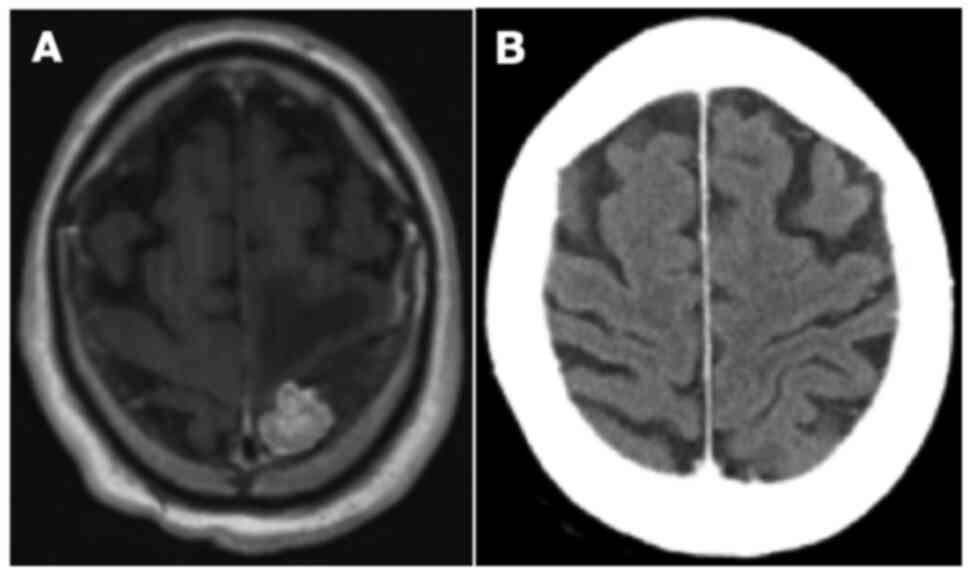

In mid-2019, approximately 3 years post-treatment, the patient began to notice a persistent, left-sided headache accompanied by short-term memory deficits. Physical examination demonstrated left-sided cerebellar dysfunction with nystagmus and clumsiness on heel-to-toe walking. Restaging investigations identified a new solitary mass measuring 3.6 cm with a broad dural base overlying the lateral left temporal and occipital lobe (Fig. 2A). No other evidence of intrathoracic or intraabdominal disease was appreciated. Neurosurgery was consulted but did not recommend surgical resection given the high risk of morbidity, particularly Wernicke's aphasia. The patient thus underwent stereotactic radiation to the solitary brain metastasis, 30 Gy in 5 fractions (Table SI). Follow-up MRI imaging demonstrated positive response to treatment with a gradual decrease in the size of the mass. However, there was also subsequent evidence of evolving radiation necrosis in the treated area, associated with mild memory loss and word-finding difficulties (Fig. 2B). As these symptoms were overall quite minor and improved spontaneously with time, no specific treatments for radionecrosis were implemented.

Figure 2.

(A) Axial T1-weighted MRI of the head with contrast showing a large mass with a broad dural base overlying the lateral left temporal and occipital lobe. (B) Axial T1-weighted MRI of the head with contrast showing an area of heterogenous enhancement within the left temporal lobe representing radionecrosis 8 months after completion of stereotactic radiation.